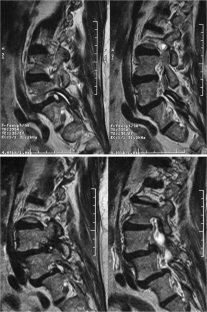

Atypical, unusual, and misleading imaging presentations of spondylolysis

Although lumbar spondylolysis is a widely known and easily recognizable condition in its typical presentation, there are some less well-known forms that may occasionally be challenging and/or demand special attention on imaging. Examples include: acute and/or incomplete lesions; unilateral defects; lesions at unusual levels (cervical, upper lumbar, and multi-level spondylolyses); iatrogenic lesions; non-isthmic spondylolysis; and spondylolysis related to underlying diseases. In addition to their atypical, uncommon or confusing imaging presentations, these forms of spondylolysis are far rarer than the classic type and have been described, to a great extent, in the surgical literature, thus reducing the awareness of radiologists about them and raising the potential for misdiagnosis and inadequate treatment. In this review the authors address these special manifestations of spondylolysis, stressing the more important features to be considered in the differential diagnosis and the impact of a precise diagnosis of spondylolysis on the patient’s care.